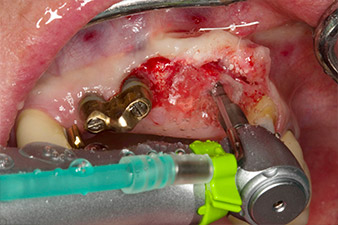

Motorized placement of the implant

Fig. 4: Motorized placement of the implant with the WS-75 L contra-angle handpiece at a ratio of 20:1 (programme P5).